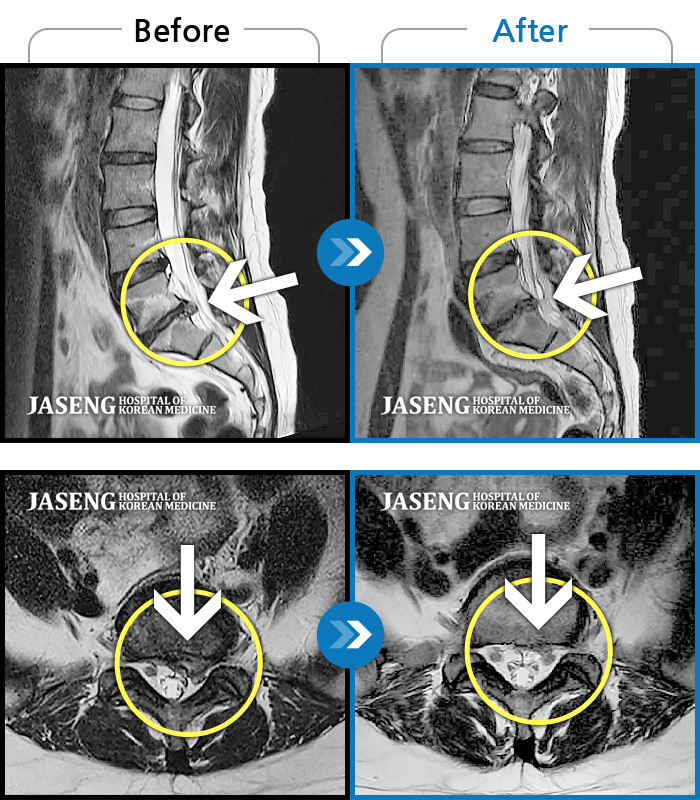

허리디스크

잠실 · 한상욱 원장

허리통증과 함께 좌측 엉치, 허벅지, 종아리 후면으로 저림이 심하여 걷기가 힘들어요.

촬영시기

2021.09.14 ~ 2022.05.14

2022.05.24

조회수 149